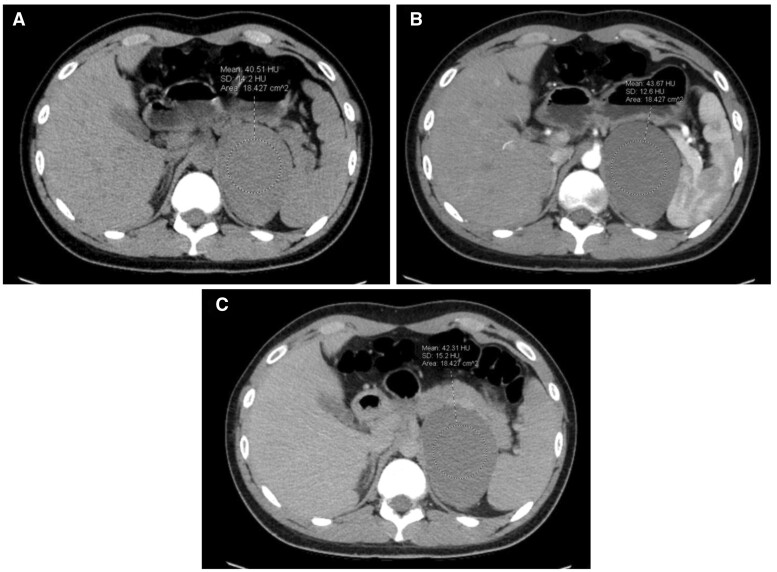

Bronchogenic cysts are rare lesions that form during early embryogenesis and are commonly located in the mediastinum. Retroperitoneal bronchogenic cysts (RBs) are exceptionally rare, with only a handful of cases reported in the modern literature. Here, we report an RB found incidentally on imaging in a patient with suspected nephrolithiasis. We also review the unique imaging and histopathological findings of this entity and discuss why prophylactic surgery is considered the treatment of choice.